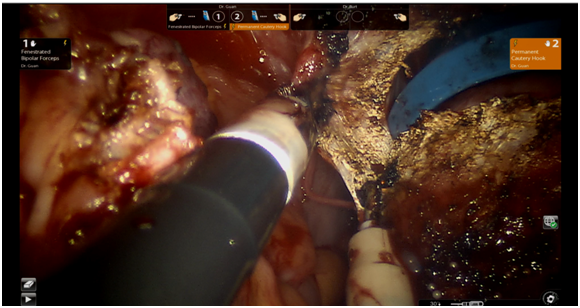

The patient underwent Da Vinci single incision laparoscopic hysterectomy (robotic-assisted total hysterectomy) with bilateral salpingectomy. The hysterectomy was modified by performing colpotomy prior to uterine artery cauterization and cardinal ligament transection (Figure 1) (Figure 2).

Figure 1 Intraoperative picture showing colpotomy done prior to uterine artery ligation.